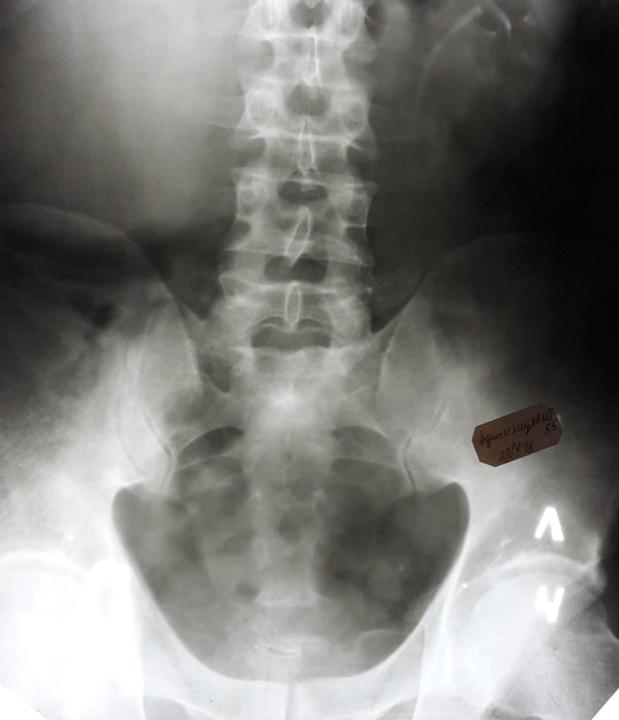

Болезнь Бехтерева

Анкилозирующий спондилартрит – заращение всех суставов позвоночника.

Обызвествление продольных связок делает такой позвоночник неподвижным.